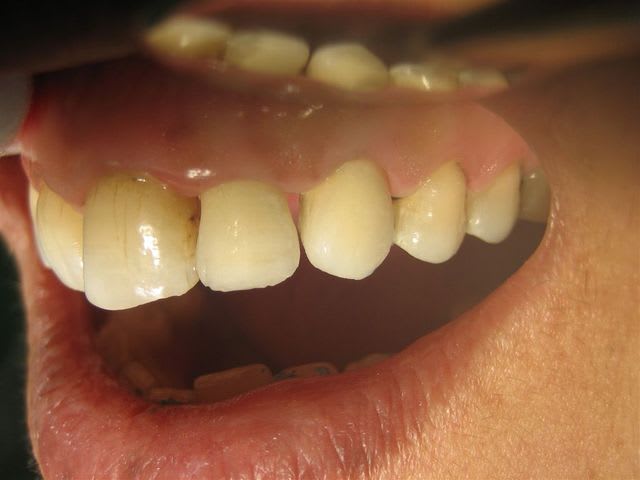

... un autre cas, mais ça ressemble toujours à ça >

Dans des teintes assez soutenues et peu translucides je trouve que la ccm avec ce type de joint rivalise bien avec les techniques plus "modernes"...